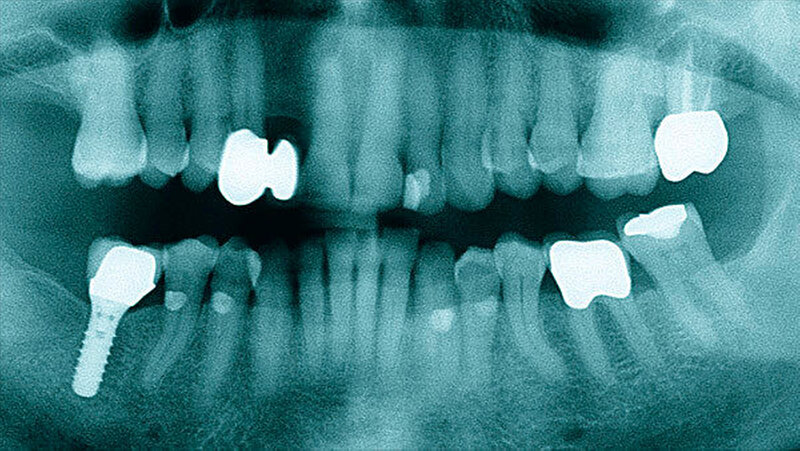

Der intraorale Befund zeigte neben einer moderat chronischen Parodontitis ein nekrotisierendes und ulzerierendes Schleimhautareal in regio 32 bis 35 (Abbildung 1). Überdies konnte eine Sondierungstiefe von 6 mm zwischen 32 und 33 sowie ein Lockerungsgrad von 1 bis 2 an den Zähnen 32 bis 34 bei positiver Sensibilität erhoben werden, wobei zumindest 2D-radiologisch kein Knochenabbau vorlag (Abbildung 2). Aufgrund des deutlich reduzierten Allgemeinzustandes des Patienten entschieden wir uns für eine stationäre Weiterbehandlung. Ein kurz darauf angefertigtes Blutbild zeigte unter anderem einen Hämoglobin-Wert von 5,2 mmol/l (Referenzbereich 8,6 bis 12 mmol/l), einen Hämatokrit-Wert von 0,24 (Referenzbereich 0,4 bis 0,51), einen Kernschatten-Wert von 40 Prozent (Referenzbereich 1 Prozent ) sowie einen CRP-Wert von 53,1 mg/l (Referenzbereich 5 mg/l).

Nach 48 Stunden i.v.-Antibiose und intensiver Hygienisierung (Abbildung 3) erfolgte die Abtragung der Gingivanekrose unter laufender Dabigatran-Medikation. Die sich von Zahn 32 bis 35 vestibulär und interdental erstreckende Nekrose wurde schonend entfernt (Abbildung 4). Eine Mitbeteiligung des Alveolarknochens war nicht erkennbar. Im Anschluss erfolgte eine chemische Dekontamination der Wunde mit Betaisodona-Lösung sowie der primäre Wundverschluss mittels modifiziertem koronalen Verschiebelappen (Nahtmaterial: Resolon 4.0, Resorba Medical GmbH). Die Zähne 32 bis 34 wurden aufgrund ihrer geringgradigen Lockerung belassen und mittels Säure-Ätz-Technik primär durch Schienung stabilisiert. Abschließend erfolgte die Abdeckung des OP-Situs mit einer Verbandsplatte, in welche im vestibulären Bereich eine Aussparung eingearbeitet wurde (Abbildung 5).